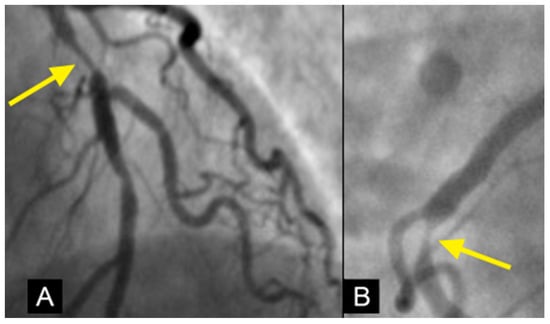

Conventional Coronary Imaging. Currently, angiography is considered the gold standard for the diagnosis of coronary artery disease, providing detailed visualization of coronary luminal stenosis (Figure 2) [3]. However, angiography is limited to static imaging, offering no insights into the dynamic processes driving development of lesions, the mechanism of their anatomical distribution, or the factors governing their progression or regression.

Figure 2. The left anterior descending (LAD) artery exhibits severe narrowing in its proximal segment (indicated by an arrow), while the right coronary artery (RCA) demonstrates a subtotal lesion in its mid-segment. Current angiographic techniques capture these lesions but fail to provide critical insights into their formation mechanisms or potential progression over time. (A) The lesion in the proximal LAD has a characteristic “rat tail” appearance—featuring progressively severe narrowing in the distal direction. (B) The mid-RCA lesion has a “reversed rat tail” pattern, characterized by more severe narrowing proximally and a gradual reduction in severity distally. WHY?